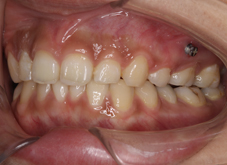

上の前歯が前方へ突出していることと、前歯にでこぼこが認められます。上は前歯を後方へ引っ込めるために第一小臼歯という歯を抜歯しています。

上の前歯のでこぼこは改善し、前方への突出(出っ歯)も改善しています。

前歯の突出とでこぼこを改善するために上の第一小臼歯という歯を抜歯して治療を行っています。前歯の突出はだいぶ改善しています。

装置を外した時の写真。前歯の突出もでこぼこも改善しています。